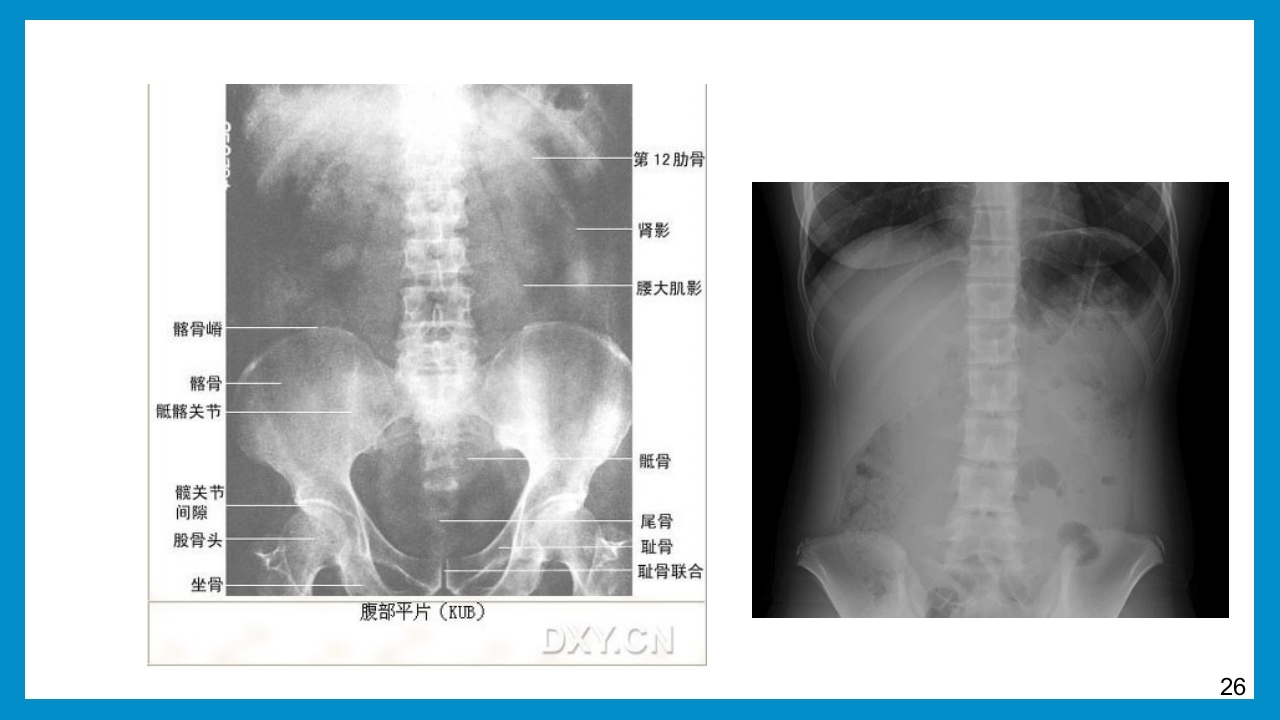

泌尿外科 规培生 :xx 指导老师:xxx 泌尿外科常见检查 泌尿系B超 尿动力学检查 膀胱镜 泌尿系CT 静脉肾盂造影(IVP) 腹部平片(KUB) 磁共振尿路造影(MRU) 【泌尿系B超】 B型超声系无创检查,作为泌尿、生殖系统疾病的筛选 方法广泛用于诊断、介入治疗和随访,具有重要价值。 常规用于肾上腺、肾、膀胱、前列腺、精囊、阴茎和阴囊疾患。 3 【泌尿系B超】 临床意义 彩色多普勒超声仪可确定动、静脉走向,清楚地显示血管内血流情况。 可选择肾实质切开部位。 临床应用对肿块性质的确定、结石和肾积水的诊断、残余尿测定及前列腺体积 测量等,能提供正确信息。 B型超声引导下可行穿刺、引流及活检等操作 4 检查注意事项 【泌尿系B超】 一般要求患者检查前2~3小时饮水 500~800m...